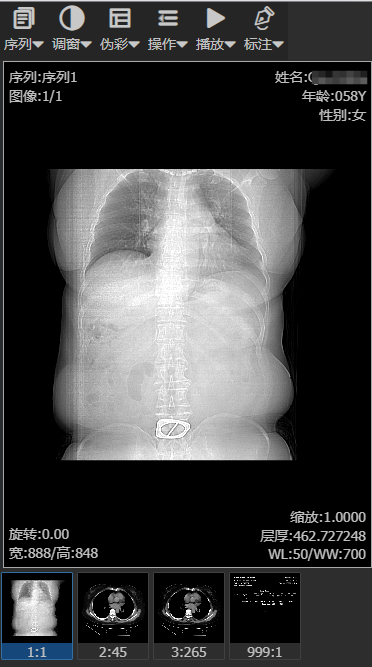

实现通过浏览器浏览Dicom影像阅片。主要功能:

支持标准DIcom影像的2D浏览,预设窗位,伪彩,序列间,序列内多种布局方式。

影像处理,提供影像翻图、缩放、移动、透镜、反相、旋转、截图等操作

影像测量,提供箭头、直线、十字架、角度、Cobb、心胸比、椭圆、矩形、勾画,橡皮擦、CT值等数据的测量

支持影像的三维重建,包括多平面重建,容积漫游技术(VR)、最大/小密度投影等功能

支持影像胶片打印功能,包括DR,CT等胶片自定义布局打印

支持平板,手机等移动设备的影像浏览

前端采用vue3+element-ui进行开发,后端采用.net以及fo-dicom组件进行开发,技术交流沟通联系QQ:469116292

界面如图所示: